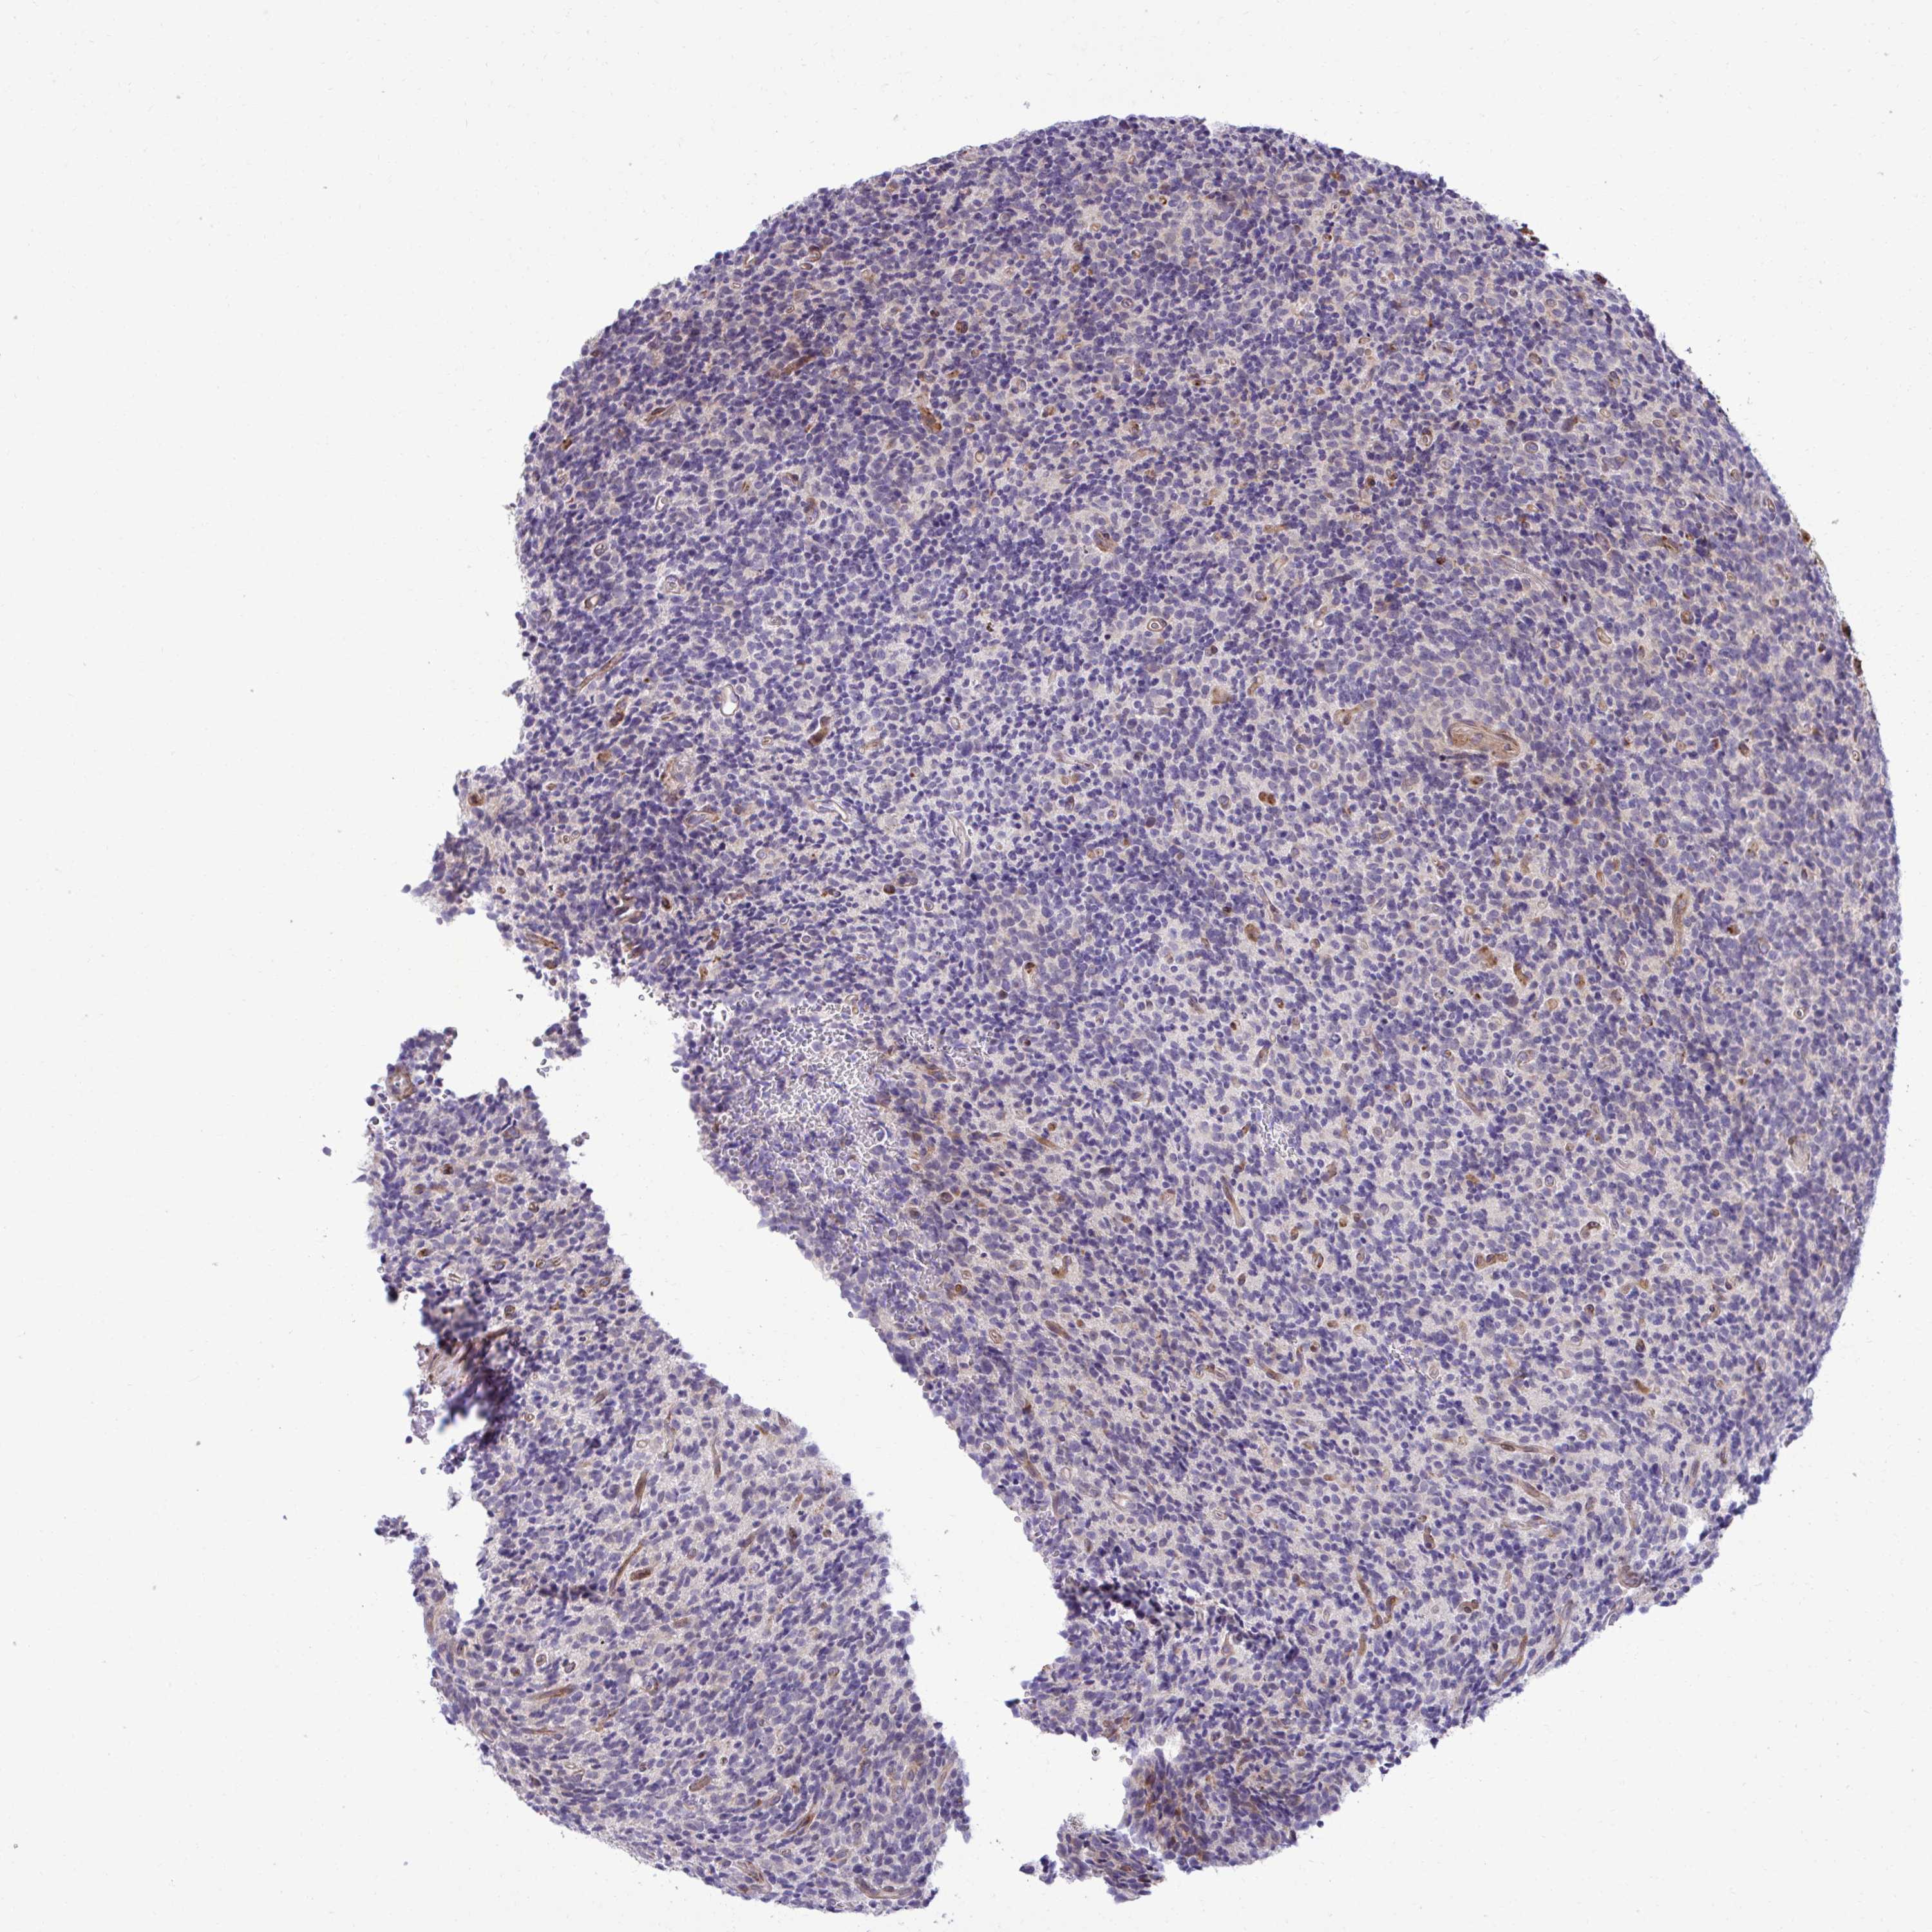

GLIOMA - Protein expressioni

A mouse-over function shows sample information and annotation data. Click on an image to view it in a full screen mode. Samples can be filtered based on level of antibody staining by selecting one or several of the following categories: high, medium, low and not detected. The assay and annotation is described here.

Note that samples used for immunohistochemistry by the Human Protein Atlas do not correspond to samples in the TCGA dataset.

Antibody stainingi

Antibody staining in the annotated cell types in the current human tissue is reported as not detected, low, medium, or high, based on conventional immunohistochemistry profiling in selected tissues. This score is based on the combination of the staining intensity and fraction of stained cells.

Each image is clickable and will lead to virtual microscopy that enables deeper exploration of all samples and also displays staining intensity scores, fraction scores and subcellular localization as well as patient and tissue information for each sample.

Antibody HPA058455

Antibody HPA061230

Staining

High

Medium

Low

Not detected

Intensity

Strong

Moderate

Weak

Negative

Quantity

>75%

75%-25%

<25%

None

Location

Nuclear

Cytoplasmic/membranous

Cytoplasmic/membranous,nuclear

Glioma, malignant, Low grade

Glioma, malignant, High grade